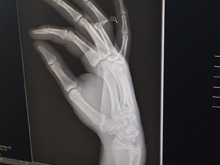

Last JV game of the season against Santa Rosa High, and also Senior Night for the Seniors. Sadly, Hunter displocated his finger right before the game! He also had a small chip fracture.